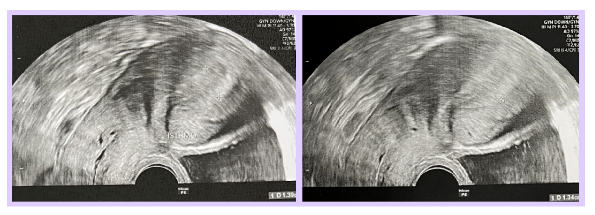

此外,客户有剖腹产史,可能导致出现子宫瘢痕憩室(Isthmocele),并且在此处发现积液。这种积液可能增加炎症的风险,并干扰胚胎在子宫内膜的着床过程。同时,客户还发现有子宫内膜息肉(Polyp),息肉可能对胚胎的着床造成阻碍,因为它会导致子宫内膜环境不平衡,从而降低试管婴儿的成功率。

- 子宫疤痕憩室